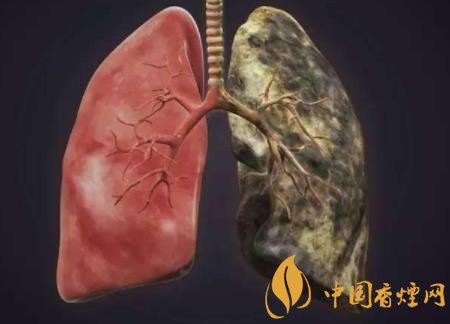

通过观察身边抽烟的人我们会发现,经常抽烟的人都会有经常咳嗽的症状,这就是肺部不能完全的排解毒素,整个呼吸道都布满了毒素。还有抽烟的时候烟中大量的焦油毒素都吸附在肺部上面,整个肺部可能都是黑色的,这时候肺部纤毛也不能很好的发挥功效,所以抽烟虽然不是直接导致肺癌的原因,可是它也是间接让肺部不能工作的原因。